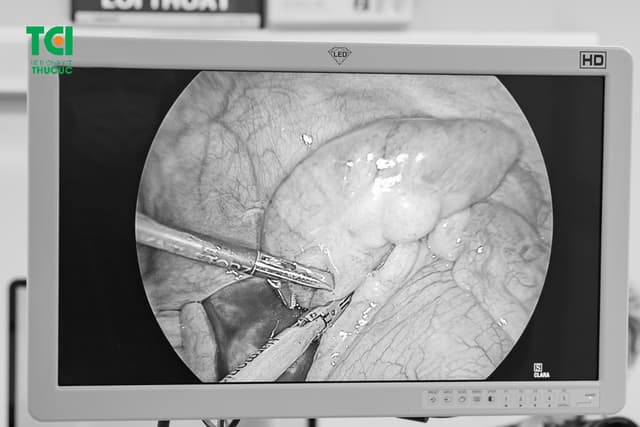

– Ứng dụng mổ nội soi trong phẫu thuật cắt ruột thừa, cắt túi mật, cắt u xơ tiền liệt tuyến, thoát vị bẹn…